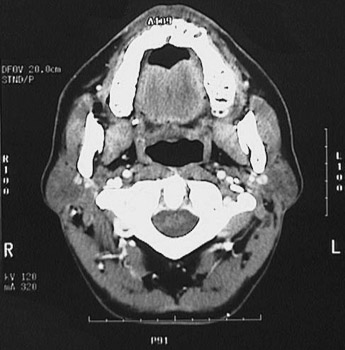

This is a normal axial head and neck CT scan demonstrating the maxilla with teeth and nasopharynx and tongue and ramus of mandible and masseter muscle and C2 and dens and spinal canal and internal jugular vein and internal carotid artery and parotid gland.